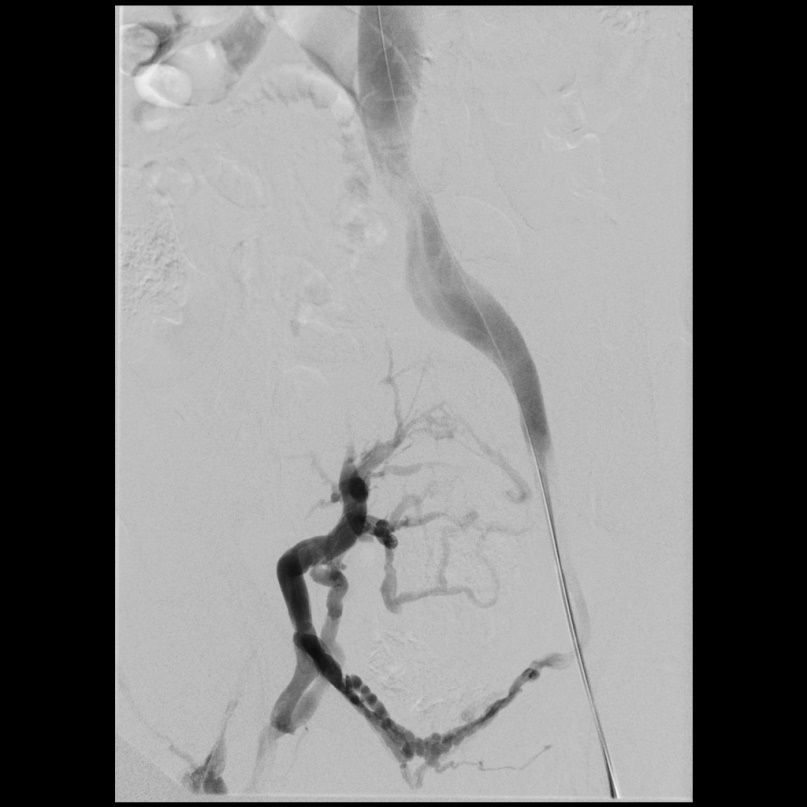

Beispiel eins Patienten mit Postthrombotischem Syndrom des rechten Beines (Schmerzen und Schwellung). Verschluss der Beckenvenen rechts (linkes Bild).

Rekanalisation mit Dilatation und Stents der rechtsseitigen Beckenvenen  (rechtes Bild). Hierdurch wieder freier Fluss in den Beckenvenen.